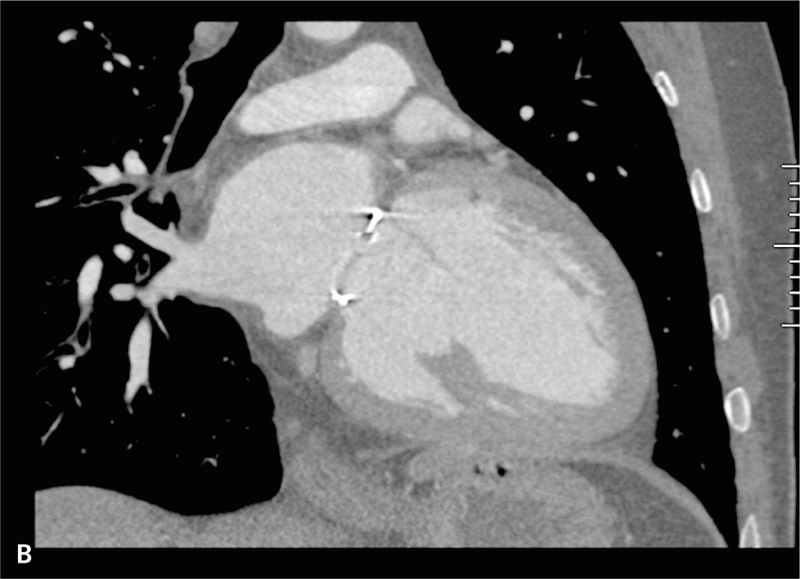

Objętość późnorozkurczowa LK przed zabiegiem wynosiła 295 cm3, a po zabiegu 222 cm3 (ryc. 3A, B, 4A, B).

RYCINA 4. Rekonstrukcja objętościowa (VR transparent) jam serca lewego. [A] Przed operacją. [B] Po operacji.

Calcium Score wynosiło 0. W tętnicach wieńcowych (LCA, LM, LAD i RCA) nie stwierdzono zmian. Parametry funkcji lewej komory były następujące: ESV 127 ml, EDV 228 ml, SV 100 ml, EF 44%, CO 6657 ml/min, czynność serca 66/min.